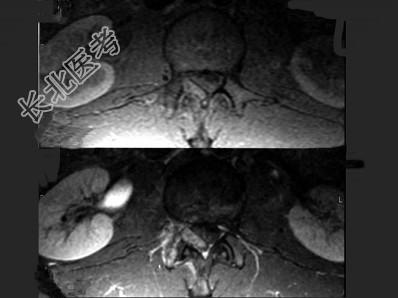

- 单项选择题男,22岁, 腰部疼痛3个月余,结合图像, 最可能的诊断是 ( )

A、腰椎结核

B、动脉瘤样骨囊肿

C、骨肉瘤

D、成骨细胞瘤

E、骨样骨瘤